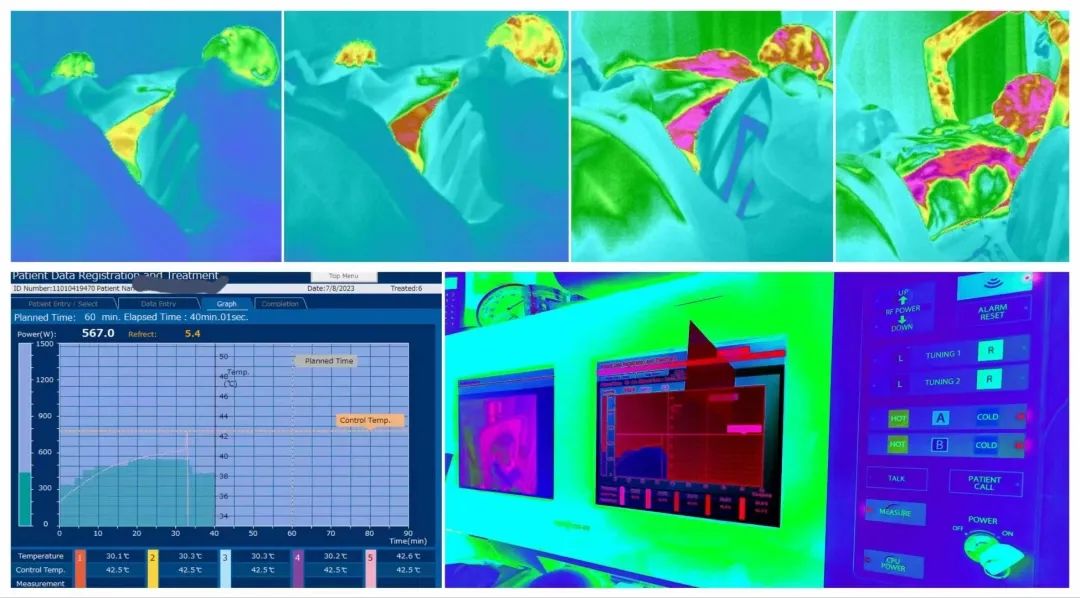

*Its precise temperature control system has an error margin of less than +(-) 0.1 degrees Celsius.

It employs efficient computer-assisted design for treatment planning and monitoring during the therapy process.

Hyperthermia: By heating the deep tissues in the target area to 43 degrees Celsius, protein denaturation occurs in cancer cells. Multiple treatments can lead to cancer cell apoptosis and alter the local tissue environment and metabolism, resulting in increased production of heat shock proteins and cytokines, thereby boosting immune activity.